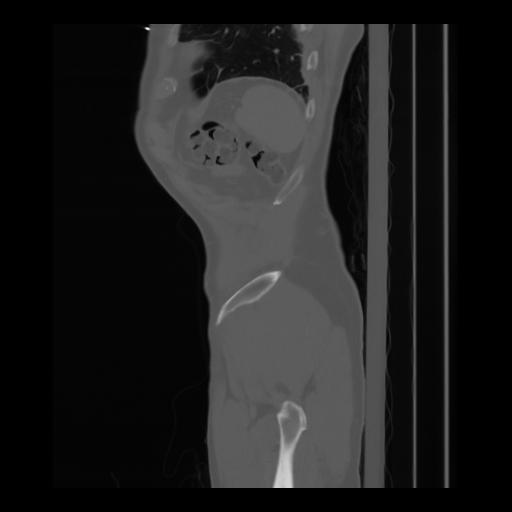

36 CUERPO,CE,Sagittal,3.000,CUERPO,Sagittal,